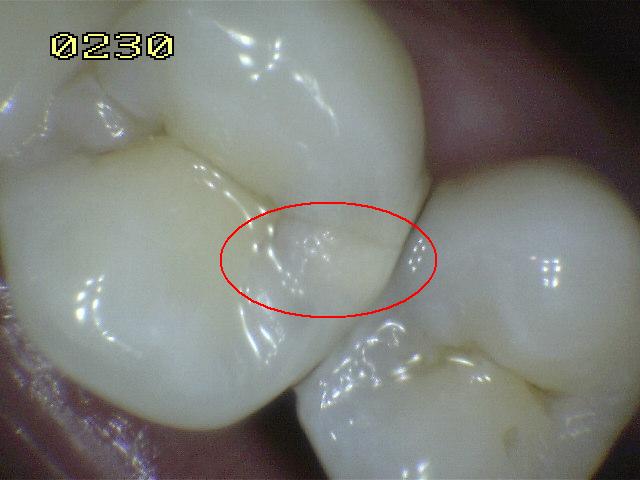

Código 3

(Caries Moderada): Ruptura

localizada del esmalte debido a caries sin dentina visible.

-

La superficie seca muestra una perdida detectable de la

estructura del esmalte. El diente visto en estado

húmedo pueden tener una clara opacidad de caries (mancha blanca

/ marrón)

Una

sonda paeriodontal puede deslizarse sobre la

lesión para comprobar micro-cavidad (pérdida de la

integridad de la superficie de esmalte < 0,5 mm.)